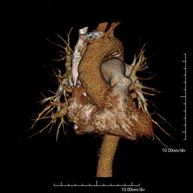

- Angio-TC Cardíaco o TC Cardíaco

El angio-TC Cardíaco o Coronariografía no invasiva es una prueba diagnóstica que consiste en el estudio de las arterias del corazón o arterias coronarias mediante el empleo de un equipo de TC Multidetector de última generación y de un contraste yodado, obteniendo imágenes bi y tridimensionales. El TC Multidetector o TCMD permite una adquisición de imágenes tan rápida, que se pueden valorar las arterias coronarias con una alta precisión anatómica: estrechamientos o estenosis, calcificaciones, variantes anatómicas, etc., ya que gracias a su rapidez evita el artefacto que provoca el movimiento constante del corazón (tarda menos de diez segundos en adquirir unas 1000 imágenes). La información obtenida precisa de un tratamiento en estaciones de trabajo con programas especializados en la reconstrucción de las arterias coronarias que permiten valorar el número, la localización y las características de las lesiones. Toda esta información se obtiene de manera no invasiva: solo se requiere la punción de una vena periférica (en el brazo). Es necesario que la frecuencia cardíaca no supere los 75 latidos por minuto, por lo que algunos pacientes deberán realizar un tratamiento previo con un fármaco betabloqueante.

- Angio-TC Cardíaco

El angioTC Cardíaco o Coronariografía no invasiva es una prueba diagnóstica que consiste en el estudio de las arterias del corazón o arterias coronarias mediante el empleo de un equipo de TC Multidetector de última generación (64 coronas o filas de detectores) y de contraste yodado, obteniendo imágenes bi y tridimensionales. El TC Multidetector 64 o TCMD64 permite una adquisición de imágenes tan rápida, que se pueden valorar las arterias coronarias con una alta precisión anatómica (estrechamientos o estenosis, calcificaciones, variantes anatómicas, etc.), ya que, gracias a su rapidez, evita el artefacto que provoca el movimiento constante del corazón (tarda menos de diez segundos en adquirir unas 1000 imágenes). La información obtenida precisa de un tratamiento en estaciones de trabajo con programas especializados en la reconstrucción de las arterias coronarias que permiten valorar el número, la localización y las características de las lesiones. Toda esta información se obtiene de manera no invasiva: sólo se requiere la punción de una vena periférica (en el brazo). Es necesario que la frecuencia cardíaca no supere los 75 latidos por minuto, por lo que algunos pacientes deberán realizar un tratamiento previo con un fármaco betabloqueante.